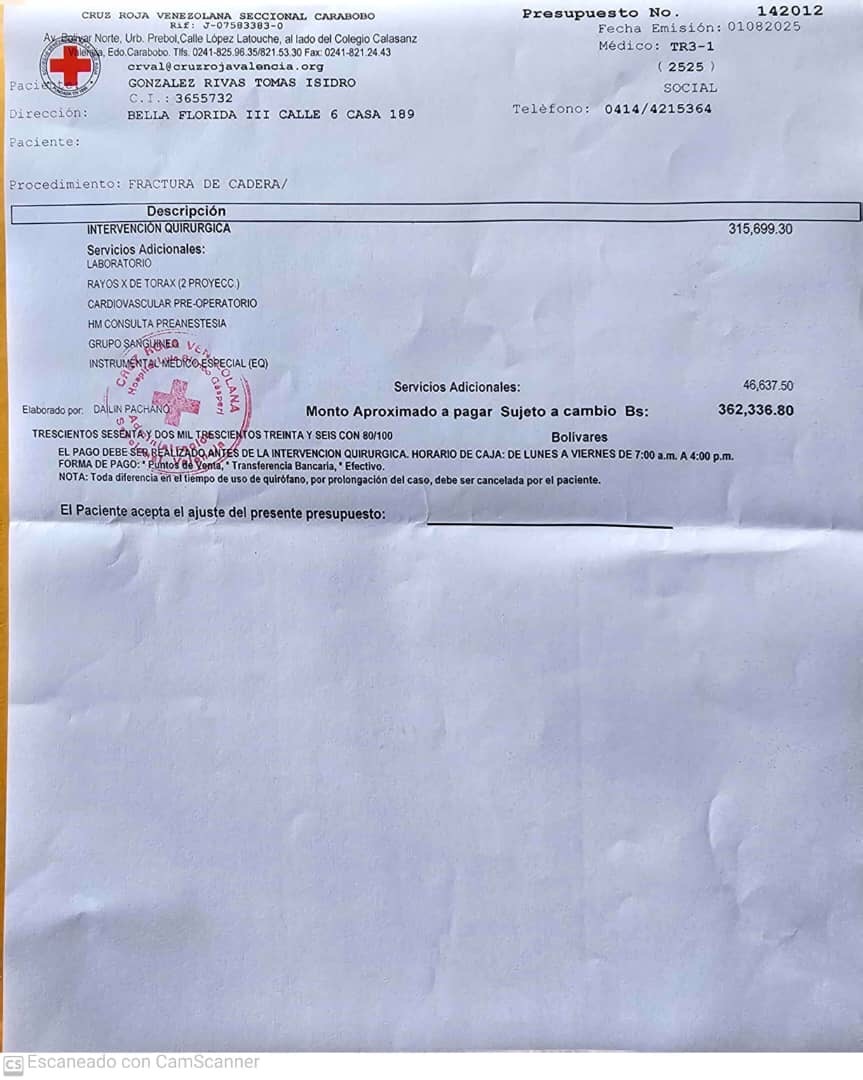

El profesor Tomás González, dedicado educador y pilar de generaciones de estudiantes en Aragua, sufrió una caída el pasado 29 de julio, que resultó en una fractura de cadera. Fue atendido de emergencia en la Cruz Roja de Valencia, donde tras los estudios correspondientes se determinó que requiere una operación urgente para la colocación de una prótesis de cadera.

El costo de la operación asciende a $2,900, la prótesis tiene un valor de $350, sin contar los medicamentos necesarios para su recuperación. Por eso, acudimos a ti, con el corazón en la mano, para pedir tu colaboración.